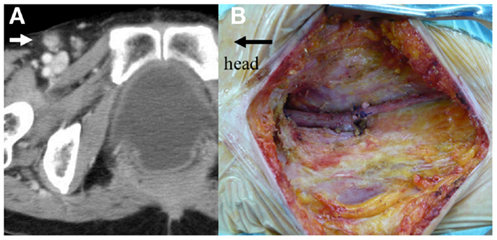

Abdomino-sacral rectal resection with permanent colostomy was performed. On laparotomy, there was no evidence of liver metastasis or peritoneal dissemination. After the large uterine myoma was raised, the tumor was palpable on the right side of the rectum. The uterine myoma was not removed. The rectum was fully mobilized and the periosteum of the upper edge of the S5 was exposed. The second step was sacral resection. The patient was placed in a jackknife position, a median incision including the anus was made, and a sacral amputation was carried out using the chisel and hammer at the upper edge of the S5. Following this, the tumor was completely resected from the pelvic floor (Figure 3).

Figure 3